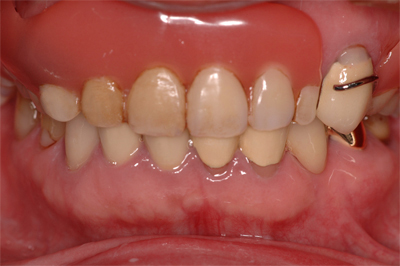

入れ歯の治療例

当院では、患者様が少ないご負担で安心して食事ができるよう、保健治療で入れ歯をお作りしています。同じ入れ歯を10年20年使っていただいている患者様も多くいらっしゃいます。

装着後

16年間使っている義歯